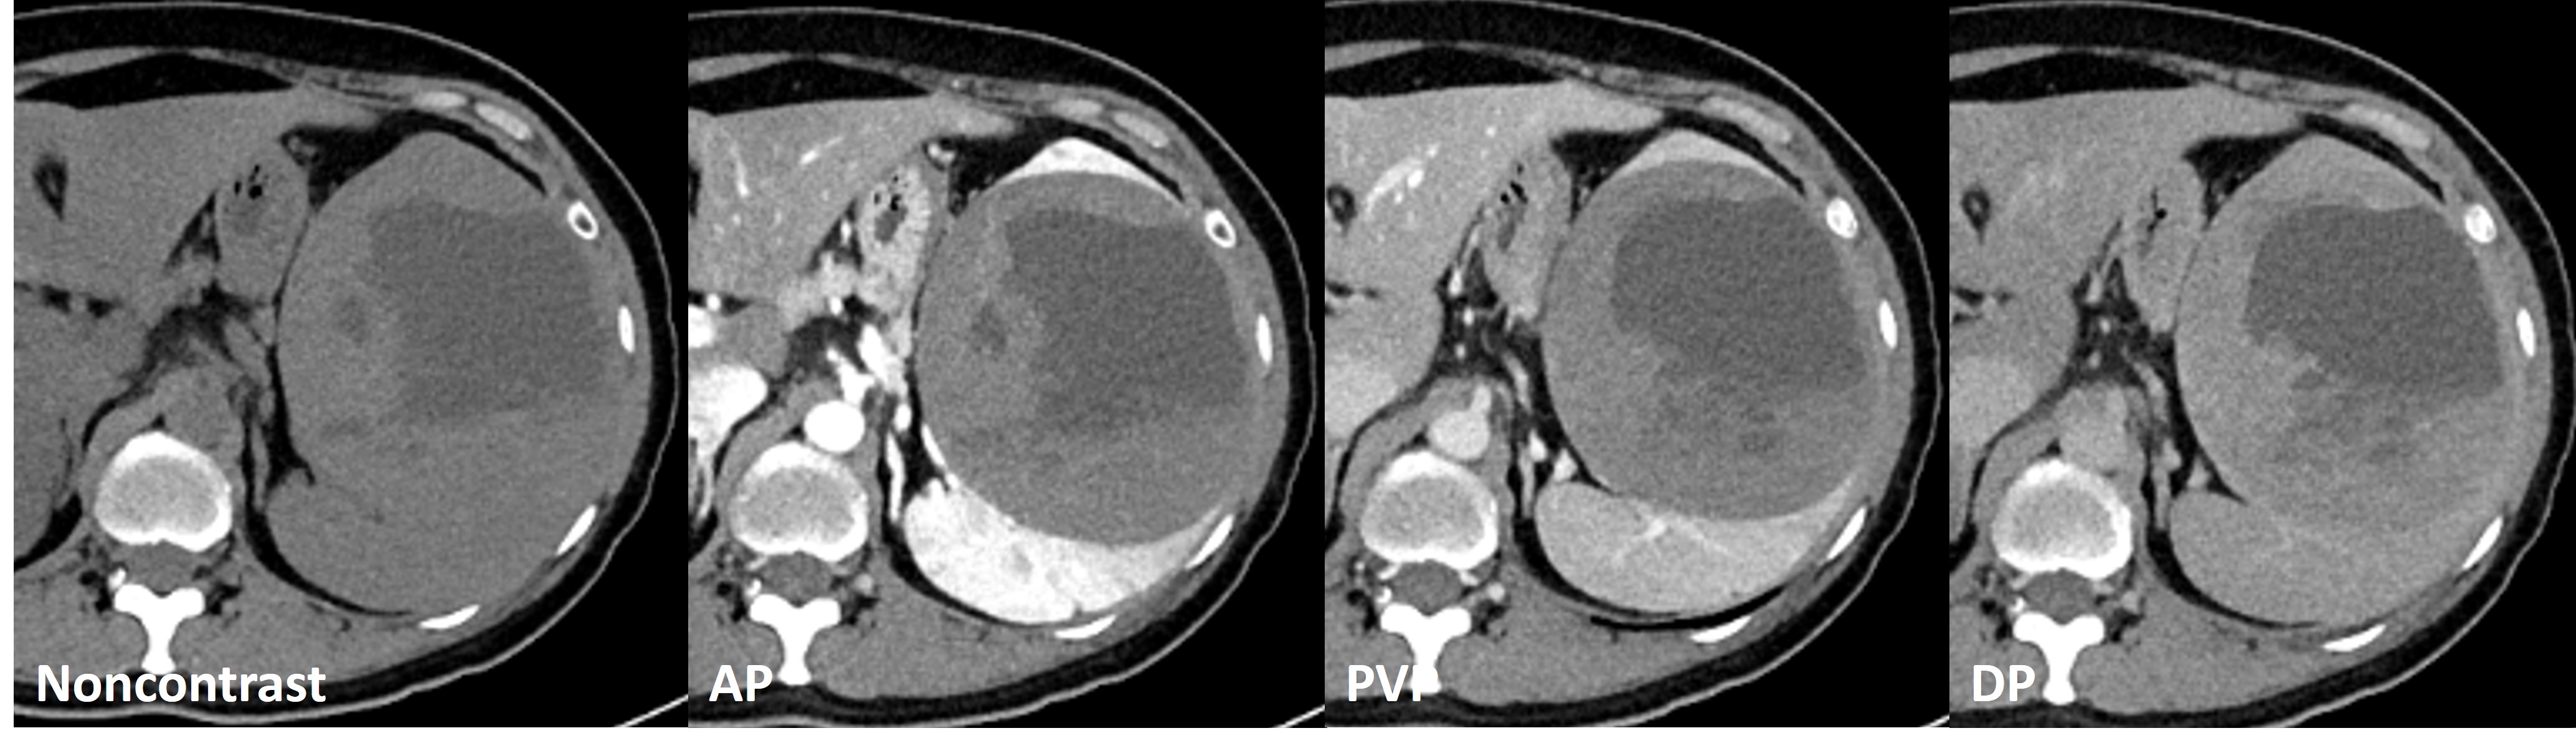

M / 54

54/M An incidentally detected duodenal ...

ABDOMEN

So Hyun Park

Seoul National ...

574

2026-02-18